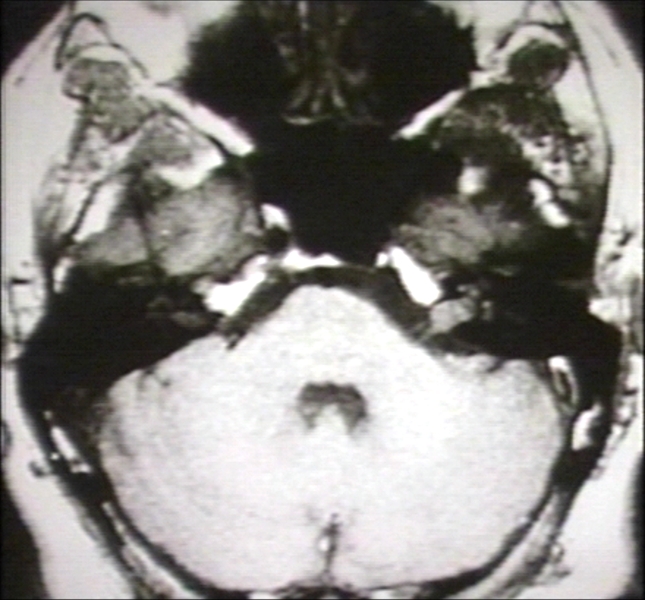

RADIOLOGY: NERVOUS: BRAIN: NEUROMA, ACOUSTIC, INTRACANALICULAR (MRI)